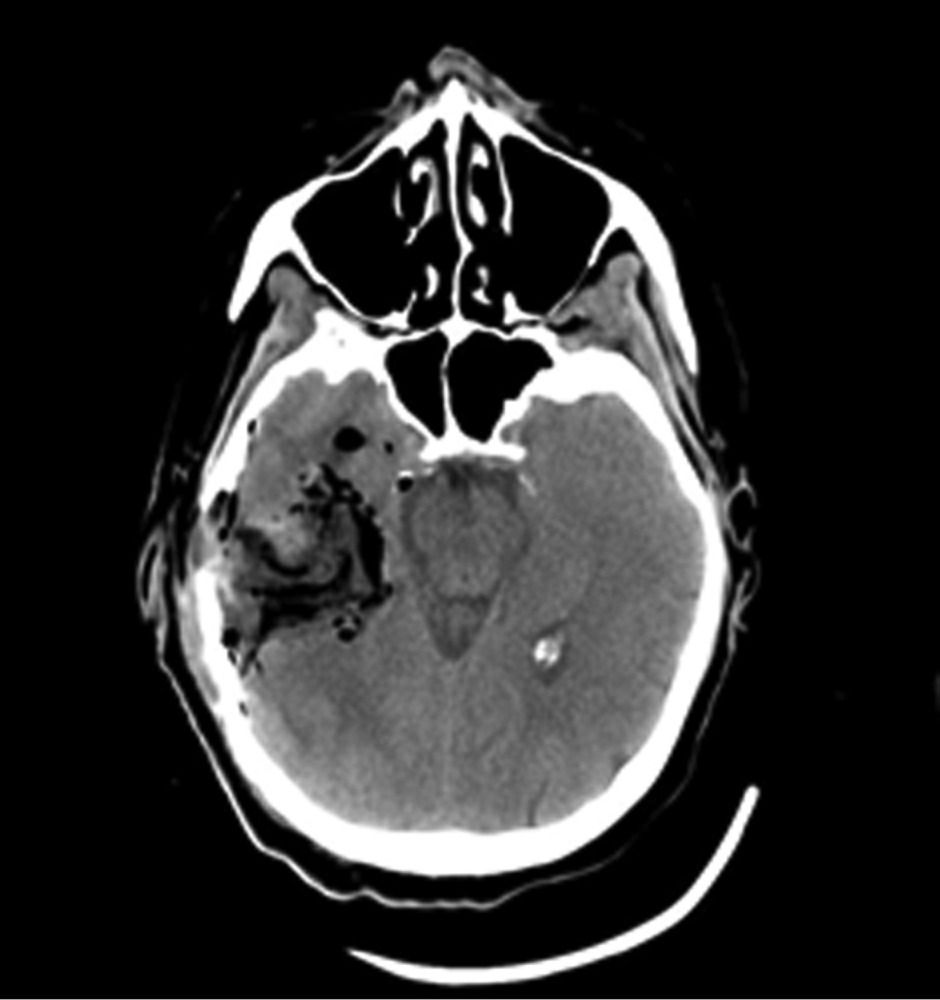

Рис. 1. Наблюдение 1. МРТ перед операцией. Внутримозговая опухоль правой височной доли с зоной перифокального отека. Опухоль, оказавшаяся при гистологическом исследовании глиобластомой (Grade IV), удалена 02.02.16. После операции пациентка была переведена в палату пробуждения отделения реанимации, где спустя 4,5 ч (через 2 ч после экстубации) развился вторичный генерализованный судорожный приступ продолжительностью около 2 мин. Приступ был купирован внутривенным болюсным введением диазепама 10 мг и вальпроевой кислоты (конвулекс) 500 мг. Экстренное КТ-исследование выявило послеоперационные изменения правой височной доли и отсутствие хирургических осложнений (рис. 2).

Рис. 2. Наблюдение 1. СКТ в 1-е сутки после удаления опухоли правой височной доли. Выявлены послеоперационные изменения в зоне хирургического вмешательства. Пациентке в 1-е сутки после операции проводился видео-ЭЭГ-мониторинг, где на фоне дезорганизации коркового ритма было выявлено замедление биопотенциалов в правой лобно-височной области (рис. 3). За следующие 13 ч записи было зарегистрировано 7 электроэнцефалографических паттернов длительностью от 2 до 4 мин, сопровождающихся появлением эпилептиформных потенциалов в виде комплексов острая—медленная волна в правой лобно-центрально-височной области (рис. 4). Шесть из семи эпизодов не проявлялись клинически. В 1 случае пароксизмальная симптоматика проявилась кратковременным (около 5 с) тоническим напряжением мышц шеи и поворотом головы вправо.

Наблюдение 2. Пациентка 64 лет за 10 мес до настоящей госпитализации была оперирована и проходила комбинированное лечение по поводу глиобластомы (Grade IV) левой лобной доли. В течение всего срока заболевания приступов с нарушением сознания или иных пароксизмальных состояний не наблюдалось. Противосудорожную терапию не получала. При контрольной МРТ за 3 нед до госпитализации выявлено увеличение размеров опухоли. Принято решение о повторном хирургическом вмешательстве. После операции 14.03.16 пациентка была переведена в палату пробуждения, где спустя 1,5 ч на фоне выхода из наркозного сна развился вторичный генерализованный судорожный приступ, который самостоятельно купировался в течение 1 мин. Проведенное КТ-исследование выявило послеоперационные изменения и отсутствие хирургических осложнений (рис. 5). В ходе суточного видео-ЭЭГ-мониторинга были выявлены диффузные изменения биопотенциалов в виде умеренновыраженной дезорганизации корковой активности, при отсутствии типичных эпилептиформных потенциалов (рис. 6). Было принято решение не назначать больной противосудорожную терапию и оставить ее на сутки под наблюдением в отделении реанимации. Клинических приступов или иных пароксизмальных проявлений не отмечено, при видео-ЭЭГ-мониторинге эпилептиформная активность не зафиксирована. После перевода в клиническое отделение приступов также не наблюдалось. Спустя 8 дней после операции пациентка в удовлетворительном состоянии выписана для продолжения химиотерапии по месту жительства.

Рис. 5. Наблюдение 2. СКТ в 1-е часы после удаления опухоли левой лобной доли. Послеоперационные изменения с зоной перифокального отека, скопления воздуха и небольшой зоной имбибиции кровью в области операции.